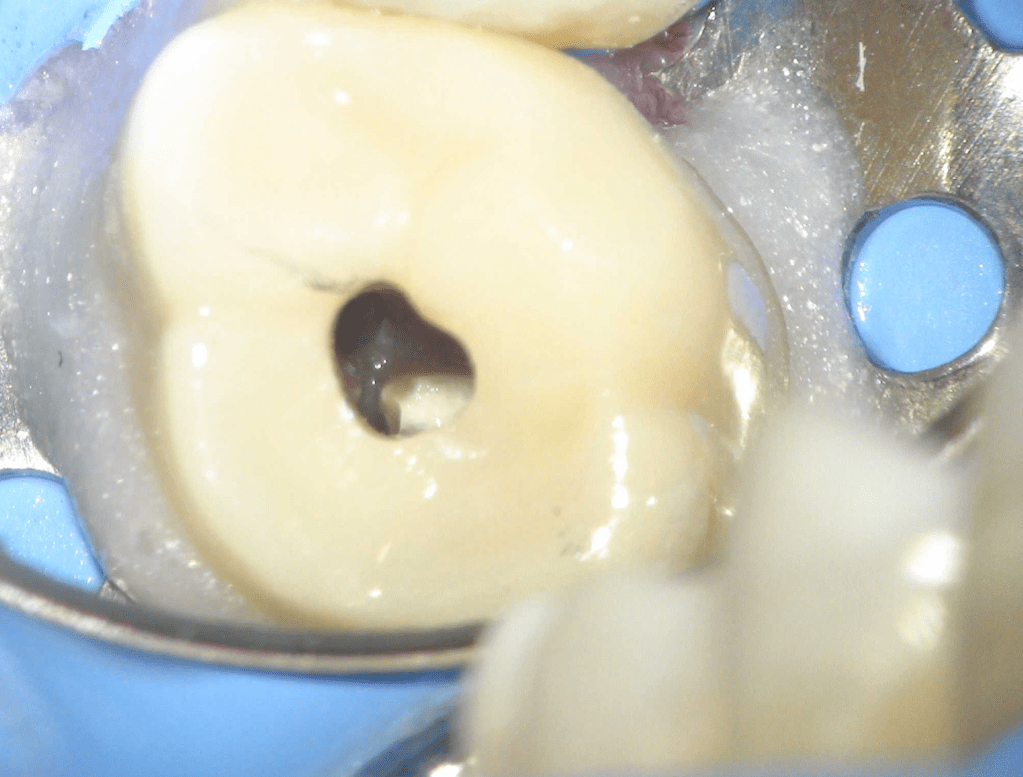

Molar superior